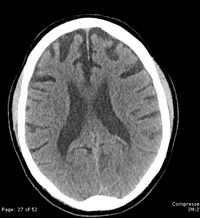

7) cuál de estas opciones describe mejor a esta imagen?

A) Una resonancia magnética de una demencia fronto-temporal

B) Un PET de una hidrocefalia

C) Una tomografía computada de un derrame cerebral en el lóbulo occipital

D) Una tomografía computada de una demencia fronto-temporal